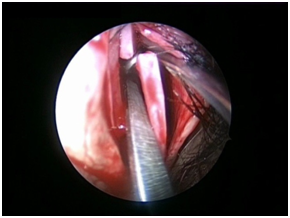

Nasal Endoscopy is done to assess the septal deviation and spurs (Figure 1) ( Figure 2). Septal infiltration is carried out with a solution of 2% Xylocaine with 1: 100,000 adrenaline in the sub-mucosal plane. It is given with a single prick at the inferior most part of the nasal septum at the junction of the septum with the floor of the nasal cavity anterior to the mucocutaneous junction. The infiltration is given at the same point on both the sides (Figure 3). The incision is always given on the deviated side. It is given anterior to the mucocutaneous junction because the skin present at that place is thick and chance of a tear of the flap is less (Figure 4). The mucoperichondrial flap is raised on the deviated side with a Freer’s elevator strictly under vision. The flap is not to be raised beyond the deviated part because the part of the septum posterior to the deviation is not under direct vision (Figure 5) (Figure 6). The caudal end of the septum is then palpated and an incision is given on the cartilage 1cm behind the columella. This 1cm of the cartilage is saved to prevent post operative tip deformities (Figure 7). The cartilage is sliced and the opposite side is entered, the mucoperichondrial flap of the opposite side is then elevated with a Freer’s elevator. A cut is given in the septal cartilage as high as possible. A septal window is created and a Ballenger’s swivel knife is taken and lodged in the place where the cartilage was cut. Creation of a septal window thus increases the area of exposure (Figure 8) (Figure 9). The flap on the non-deviated side is elevated till the bony-cartilaginous junction.

Figure 3 Infitration.

Figure 4 Skin incision.